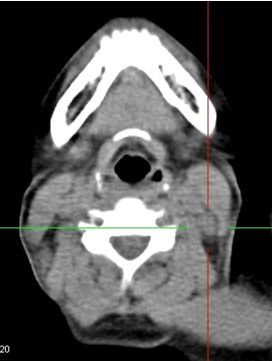

Trên lâm sàng và CT không phát hiện được hạch cổ. Nên kế hoạch điều trị là: xạ trị đơn thuần, với tổng liều vào u vòm là 70 Gy, vào vùng cổ 2 bên 50 Gy.

Trên PET/CT phát hiện hạch di căn vùng cổ trái, nên đã thay đổi giai đoạn bệnh, và làm thay đổi kế hoạch điều trị: xạ trị kết hợp hóa chất, tổng liều vào u vòm: 70Gy, liều vào hạch vùng cổ trái: 70Gy, dự phòng vùng cổ phải: 50Gy.

Hình 2: Hình ảnh PET/CT phát hiện thêm được hạch cổ phải, CT bỏ sót không thấy

Do PET/CT có độ nhạy và độ đặc hiệu cao hơn nhiều so với CT (khoảng 30% hạch cổ di căn mà lâm sàng và CT bỏ sót), nên đã làm thay đổi giai đoạn bệnh và từ đó làm thay đổi thái độ điều trị cho người bệnh.